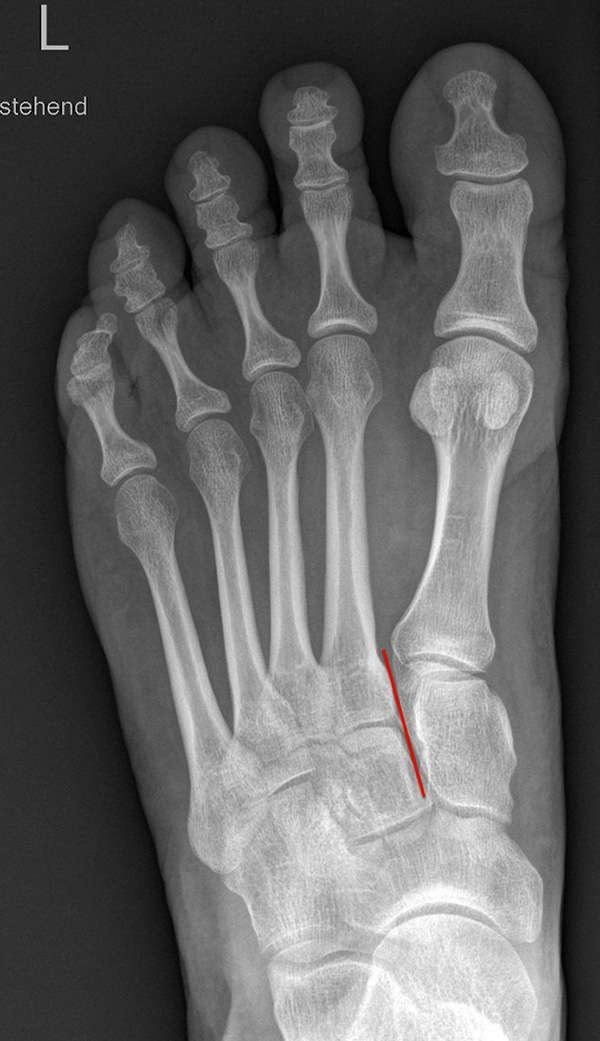

Standardisierte Röntgenaufnahmen des betroffenen Fußes, dorsoplantar (dp), streng seitlich sowie eine Schrägaufnahme werden angefertigt. Diese sollten möglichst unter Belastung angefertigt werden, da in den unbelasteten Aufnahmen insbesondere diskrete Veränderungen häufig nicht sicher zu erkennen sind.

Auf den dp-Aufnahmen sollte der mediale Rand der Metatarsale-2-Basis mit dem medialen Rand des Os cuneiforme intermedium eine homogene Linie ohne Stufenbildung bilden (Abb. 7+8). Außerdem ist auf den Abstand zwischen der Metatarsale-1- und -2-Basis zu achten. Dieser sollte nicht größer als 2 mm bzw. im Vergleich zur Gegenseite nicht mehr als 1 mm erweitert sein. In bis zu 90% der Fälle zeigt sich ein sogenanntes „Fleck sign“ (Abb. 9), ein knöchernes Fragment zwischen der Metararsale-1- und -2-Basis im Sinne eines knöchernen Ausrisses des Lisfranc-Ligaments an der Metatarsale-2-Basis 211936410. Oft liegen zusätzliche Frakturen der Metatarsalebasen oder der Tarsale vor, die ebenfalls identifiziert werden sollten. Bei jeder Mittelfußbasisfraktur sollte umgekehrt an eine Lisfranc-Verletzung gedacht werden.

Zum Lesen der Bildbeschreibung und zur Vollansicht bitte die Bilder anklicken.

In der Schrägaufnahme sollte der mediale Rand des Cuboids mit dem medialen Rand der Metatarsale-4-Basis eine homogene Linie bilden.

In der seitlichen Aufnahme ist auf Dislokationen und Subluxationen in den Tarsometatarsalgelenken sowie auf einen Verlust des Fußlängsgewölbes zu achten. Bei Instabilitäten des 1. Strahls bzw. Abflachung des Fußlängsgewölbes tritt in der Seitaufnahme die plantare Kontur des Os cuneiforme mediale tiefer im Vergleich zur Basis des Metatarsale 5. Darüber hinaus sollte die Cyma-Linie im Bereich des Chopartgelenkes in der Seitaufnahme eine harmonische S-förmige Linie bilden.